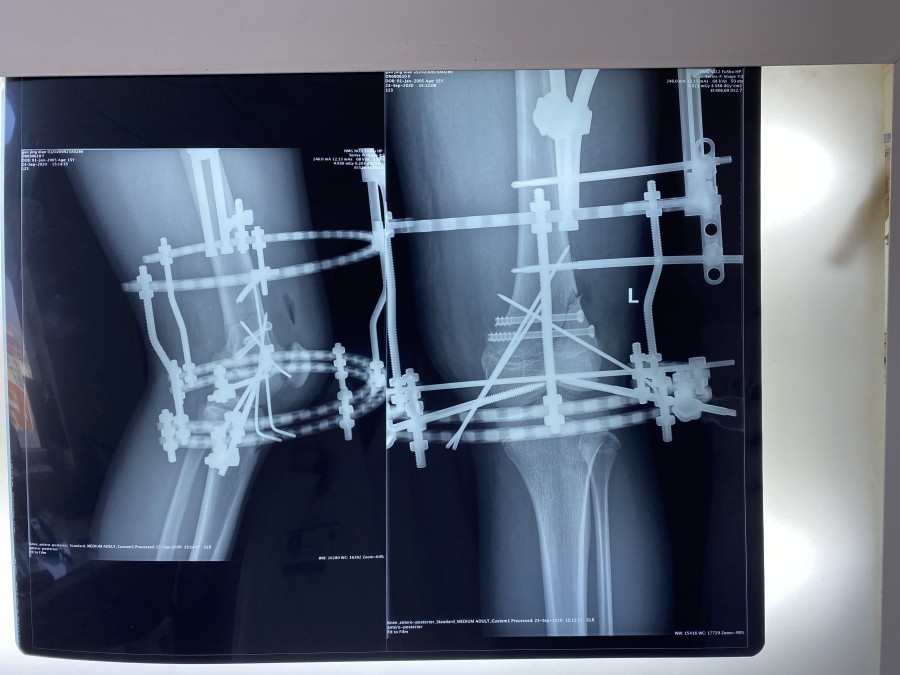

幸运的是MRI检查没有膝关节韧带和半月板的损伤。考虑到小郭的职业生涯,不能出现医源性肌肉等软组织损伤、以及运动员发达的大腿肌肉和术后快速康复的需求等等,小儿骨科团队进行了认真的术前讨论,9月21日,由韦宜山主任主刀实施了闭合复位经皮空心螺钉联合克氏针辅助Ilizarov环形外固定架手术治疗。手术非常成功,骨折端完全解剖复位,术后第1天小郭即开始床上膝关节主动和被动活动,第3天已可下地进行短时间不负重训炼,术后第10天已经可以独立扶双拐行走,10月9日,小郭顺利康复出院。术后,小郭一日三餐由我院营养部免费提供营养餐,病区护理人员专人负责陪护。